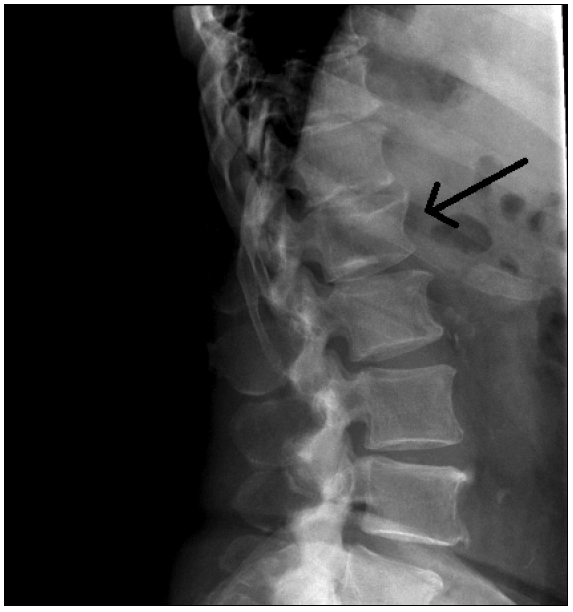

Одним из критериев диагностики остеопороза служит наличие компрессионных переломов позвонков [19, 20]. Для их диагностики проводят боковую рентгенографию грудного (Th4–Th12) и поясничного (L1–L4) отделов позвоночника (рис. 1). При этом отсутствие снижения высоты тел позвонков оценивают как стадию 0, снижение на 20–25% в одном из отделов или общее снижение на 10–15% – как стадию 1, снижение на 25–40% в любом отделе или общее снижение на 20–40% – как стадию 2 и снижение на 40% и более в любом отделе или общее снижение более чем на 40% – как стадию 3. Метод рентгеновской морфометрии обладает достаточной чувствительностью и специфичностью, а также простотой и доступностью в клинической практике [21].

Рис. 1. Компрессионный перелом первого поясничного позвонка на боковой рентгенографии.